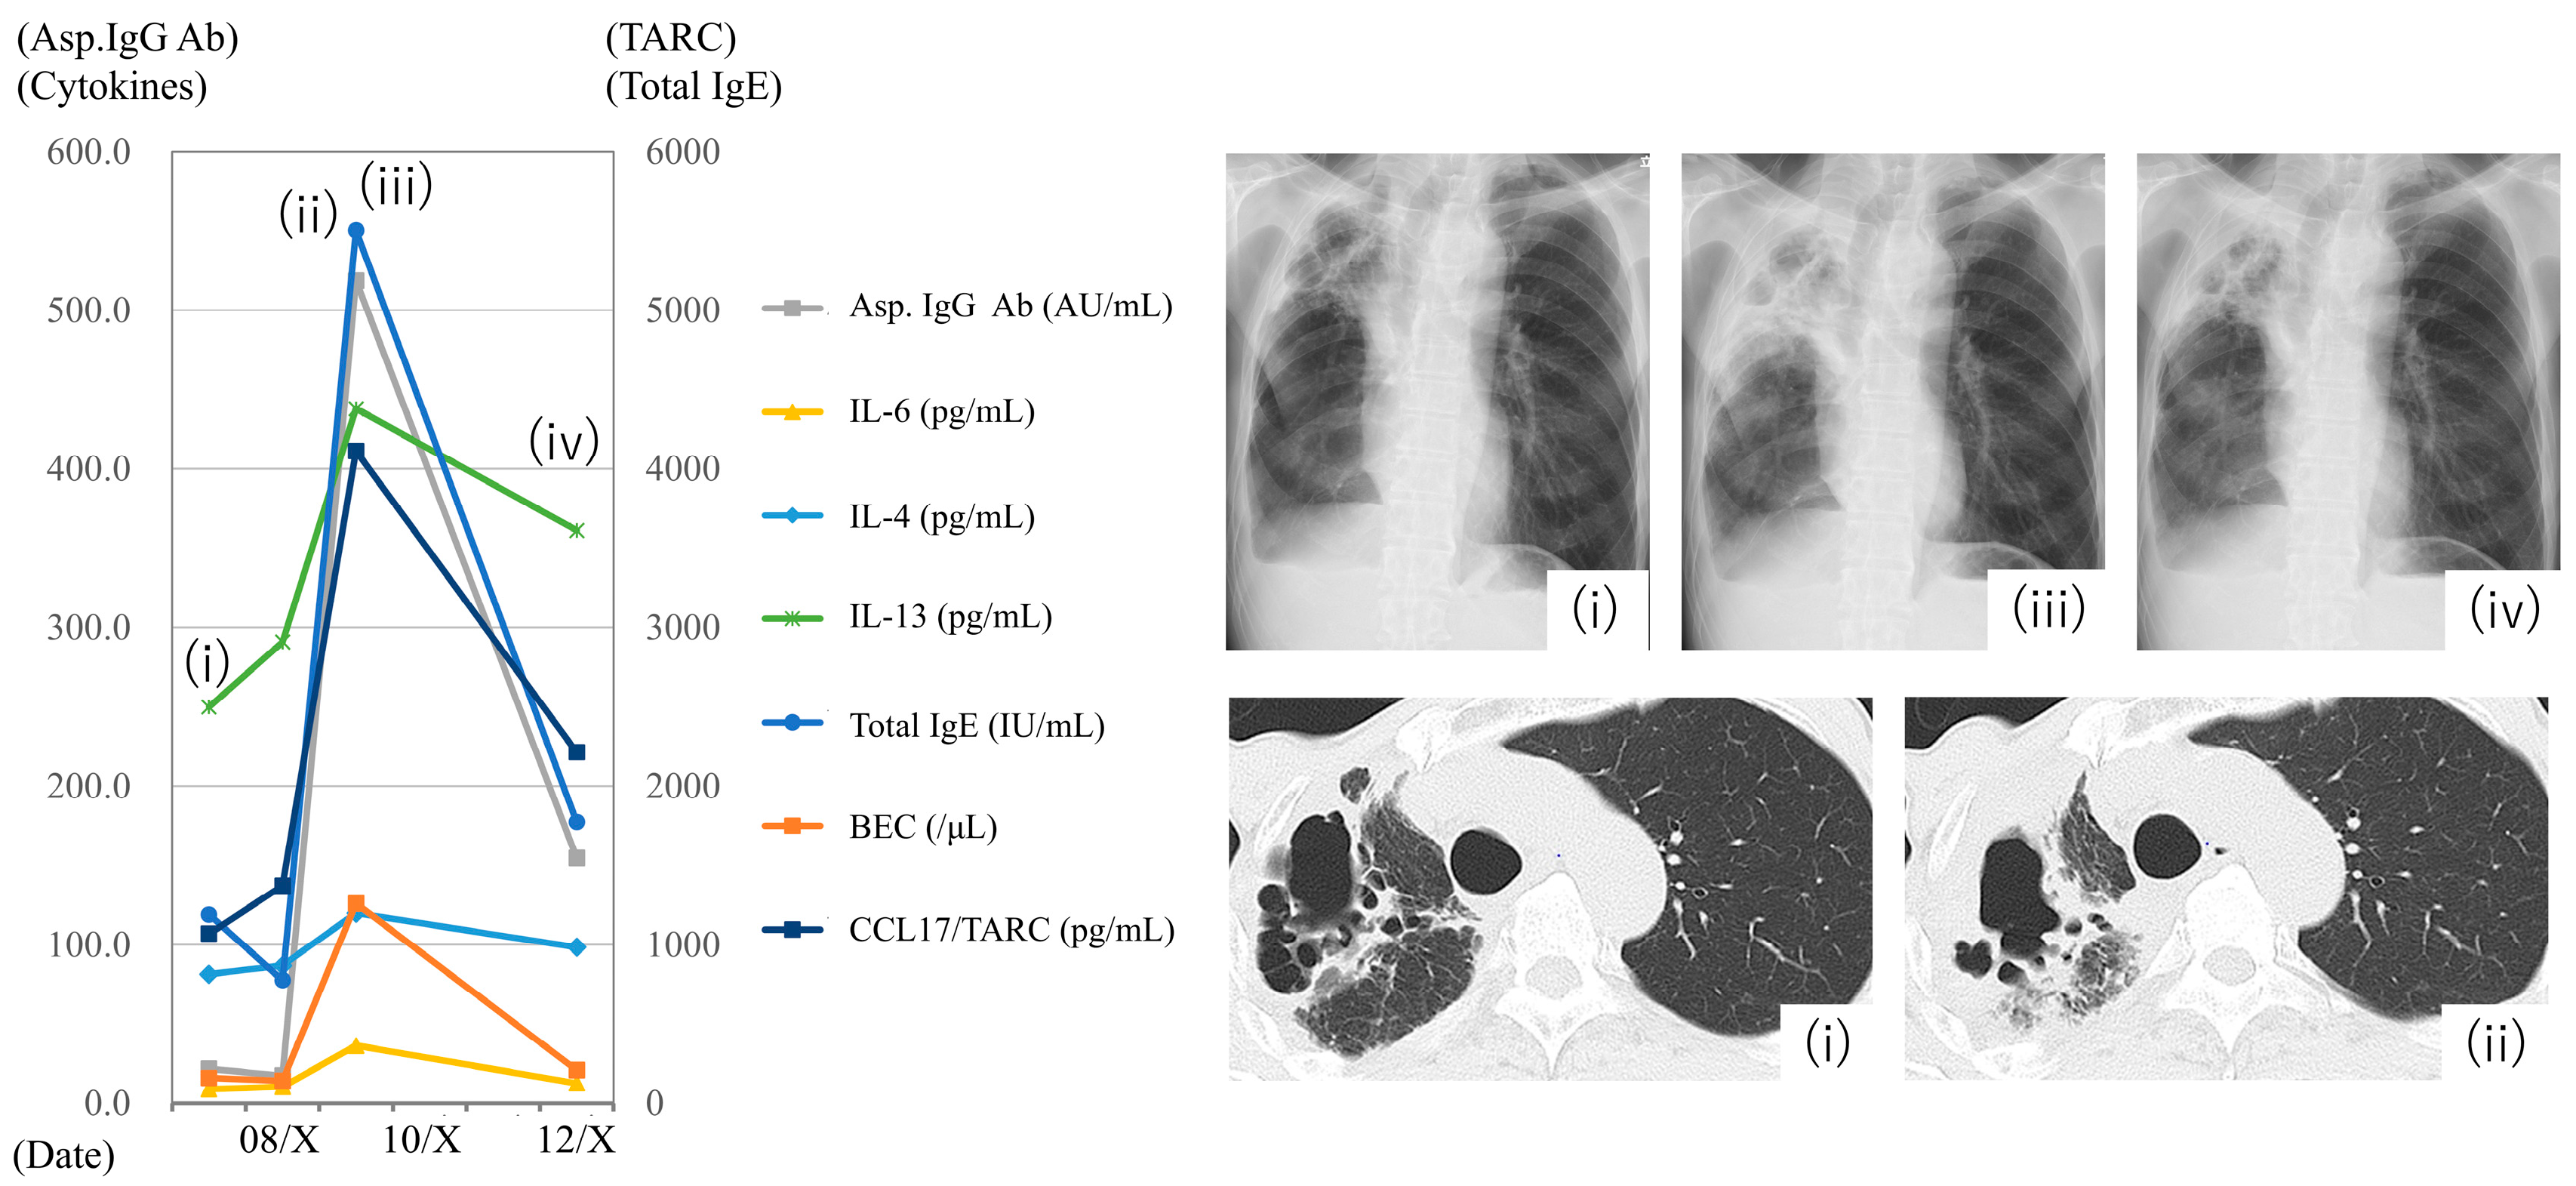

3.5. Case Presentation